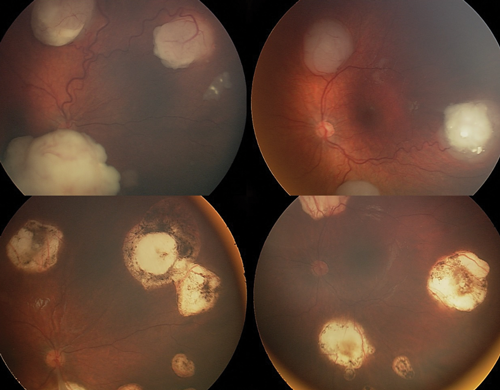

Laser treatment: Laser treatment is suitable for primary treatment of smaller tumours, or larger tumours after they have been shrunk to a treatable size with chemotherapy (chemoreduction). Laser treatment is, however, not effective for vitreous seeds (Figure 1).

Figure 1: Tumours before (above) and after treatment with chemotherapy and laser (below).

Laser is delivered through dilated pupils using the indirect ophthalmoscope or microscope. The two common laser wavelengths are 532nM green light and 810nM infrared light. Large spot 810nM treatment heats the tumour slowly (thermotherapy) to produce necrosis and is preferred by many centres [1].